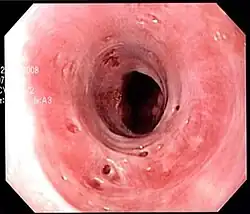

Endoscopic image of esophageal intramural pseudodiverticulosis demonstrating the flask-like outpouchings of the esophageal wall.

Esophageal intramucosal pseudodiverticulosis is typically diagnosed at the time of endoscopy of the esophagus. Endoscopy shows evidence of the pseudodiverticulae, which are typically numerous, appear like pits in the wall, and may be preferentially located in the upper esophagus.[3][5] The mucosal lining of the esophagus may be inflamed, and this can be seen on endoscopy or biopsy; the mucosa, however, may also be normal if esophagitis is not the cause of the pseudodiverticulosis. The condition must also be excluded from esophageal cancer, which may be done at the time of endoscopy, or which may require esophageal biopsy.[3]